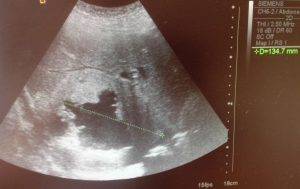

УЗИ живота и органов брюшной полости: нормы и признаки заболеваний у детей и взрослых

УЗИ органов брюшной полости (ультразвуковое исследование органов живота) – это один из наиболее доступных и информативных методов диагностики состояния различных органов брюшной полости. Практически все органы брюшной полости (печень, желчный пузырь, почки, поджелудочная железа, мочевой пузырь, селезенка) имеют достаточные размеры и плотность и хорошо отражают ультразвук, что позволяет легко сканировать их с помощью ультразвука. Во время проведения УЗИ внутренних органов определяются и их размеры, толщина их стенок, структура их тканей и составных элементов. УЗИ органов брюшной полости в любом возрасте совершенно безболезненно и безопасно.

Нормы при УЗИ печени

Во время УЗИ печени врач обращает внимание на однородность структуры печени, на крупные сосуды (например, портальную вену) и их более мелкие ветви в печени, желчевыводящие протоки, а также измеряет размеры долей печени. В норме на УЗИ печени определяются следующие показатели:

| Показатель | Норма для взрослого человека |

| Передне-задний размер правой доли | До 12,5 см |

| Передне-задний размер левой доли | До 7 см |

| Диаметр портальной вены | До 13 мм |

| Общий желчный проток | До 6-8 мм |

| Структура печени | Однородная |

| Края печени | Ровные |